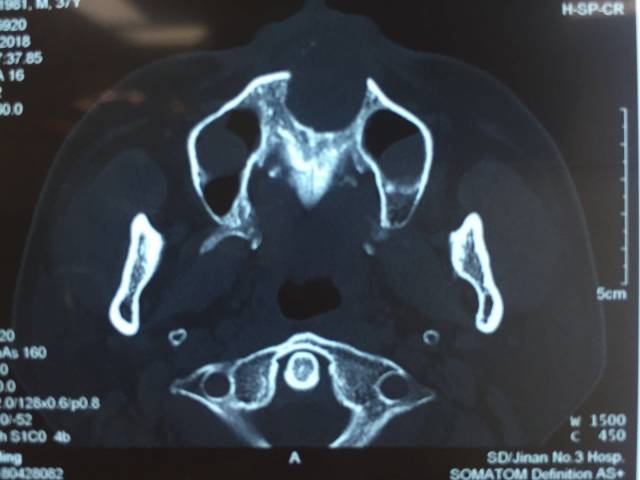

口腔科为其检查后告诉小刘「这哪里是牙龈发炎?!明明是「金屋藏娇」——上颌骨内藏了个巨大肿物」。上颌骨 X 光平扫显示「上颌骨囊性占位、双侧上颌窦囊肿」。

巨大肿物的长期压迫,严重损害了上颌周围骨质,上颌的牙齿面临「池鱼之灾」,很有可能被连根拔除。